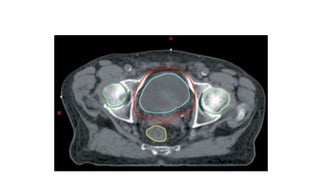

• Contouring guidelines

– GTV : primary tumour

– CTV : whole bladder and any extra-vesicle extension

– Men : entire prostate

– Women : the proximal 2 cm of urethra is also

considered s apart of target field

– PTV : 1.5-2 cm around CTV